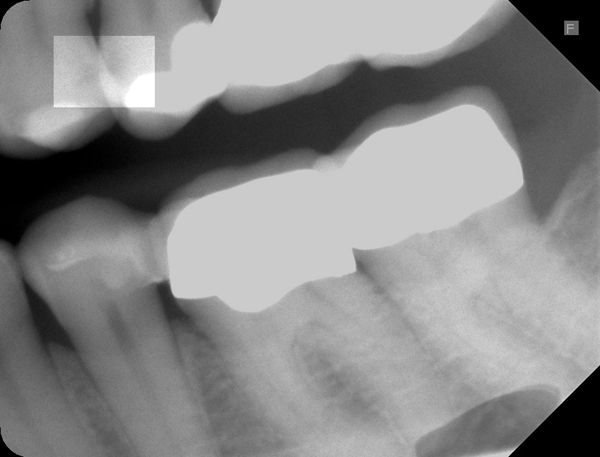

Zuerst konnte man die Karies an beiden Zähnen im Röntgenbild erkennen. Man muss allerdings genau hinsehen:

Zahnzwischenraumkaries